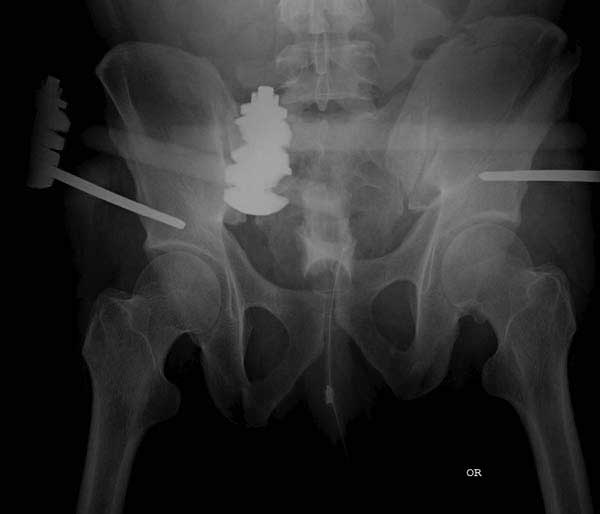

Здесь представлен случай 38 летнего больного (падение с высоты 9 метров) с нарушением тазового кольца. При поступлении для стабилизации передне-нижний аппарат наружной фиксации и на 6й день, вчера, операция из двух доступов.

Представлены снимки техники проведения стержней. Через место прикрепления прямой мышцы в Inferior Iliac Spine в направления вырезки создается жесткость. Weber clamp изнутри таза для репозиции, и фиксация после репозиции перелома крыла подвздошной кости. Наружный аппарат удален, нагрузка предполагается через два месяца.